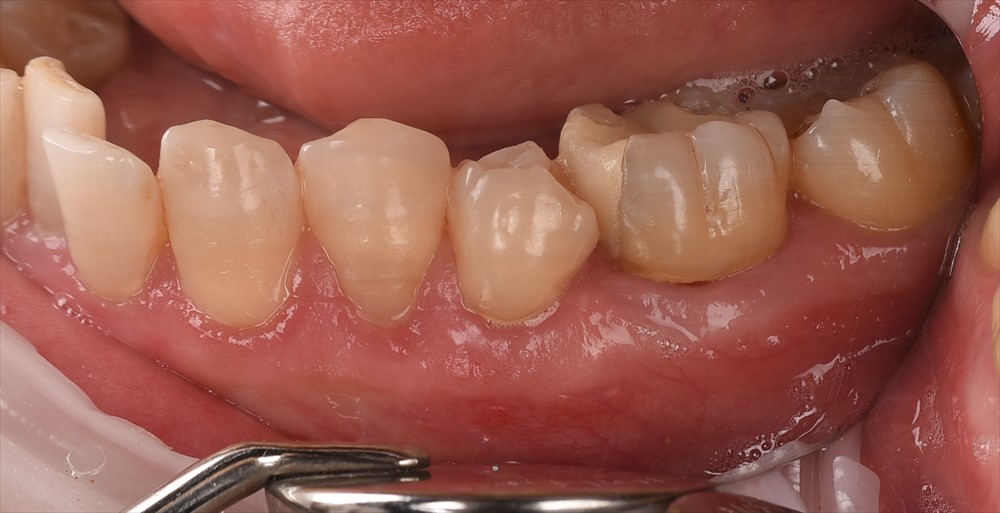

この様に左下の象牙質が露出し、何をしてもしみるとの事で①年前に来院されました。

左上の3.4.5番に歯ブラシをあてると痛い

術前